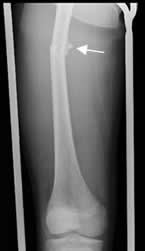

Fig 122. Consolidación retardada.

A: Rx AP. Fractura espiroidea en la tibia, que se manejó con reducción cerrada y estabilización con yeso.

B: Rx AP. Rx de control a los 4 meses, sin formación de callo óseo y los extremos no están en contacto.